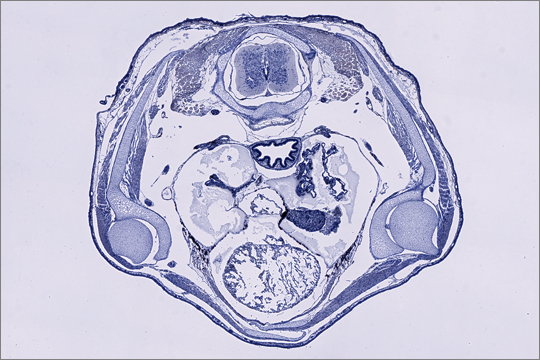

Die Leica Slide-Scanner Einheit ist ein mit MetaMoph-Software gesteuertes, vollautomatischen DM6000 Forschungsmikroskop mit dem bis zu vier Standardobjektträger auf einmal digitalisiert werden können. Da das System Bilder automatisch aus mehreren Aufnahmen zusammensetzt ist die verwendete Vergrößerung (1,25x - 100x) nicht mehr von der Größe des Objekts abhängig sondern kann frei gewählt werden.

Die speziell für histologische Serienschnitte konzipierte Software erlaubt nahezu vollautomatisches Digitalisieren inkl. Schnitterkennung, Autofokus und Aufnahmennummerierung. Bei schwierigen Proben kann die Software aber auch semi-automatisch (z.B. mit manueller Festlegung der Einzelschnitte) oder vollständig manuell (inkl. manuellen Fokus) eingesetzt werden. So wird immer ein optimales Ergebnis erzielt.